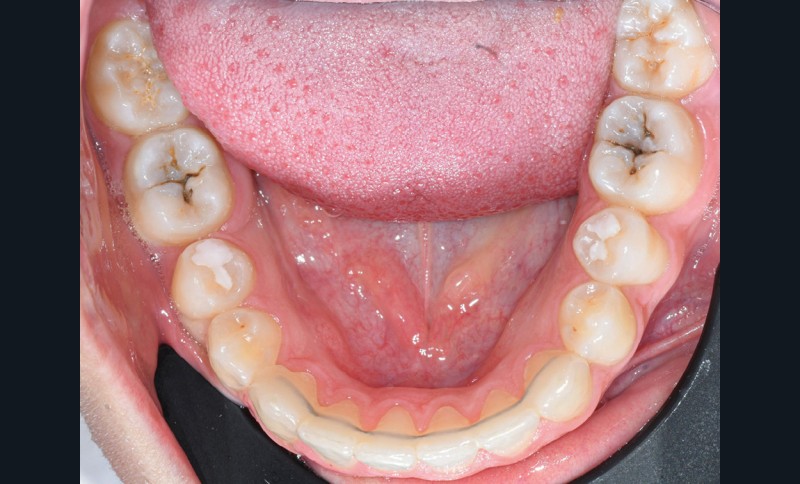

Nous détaillons la technique à travers le cas d’une jeune fille de 18 ans présentant des lésions carieuses sur quatre dents (fig. 1 à 14).

Il est tout à fait possible d’utiliser cette technique lorsque la cavité a atteint une paroi proximale. Il suffit alors de recréer d’abord le mur proximal manquant en résine composite, puis d’ajuster le tampon pour qu’il n’interfère pas avec ce dernier. La cavité de classe II se transforme alors en cavité de classe I [7].